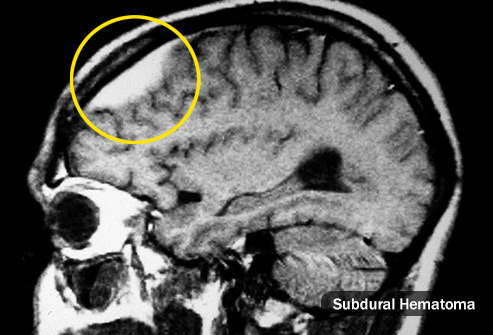

Вы ударились головой

Головные боли могут начаться сразу или через несколько месяцев после травмы. Они могут быть на месте удара или по всему черепу и могут усиливаться, когда вы находитесь в состоянии стресса. Причина не всегда ясна, но иногда слишком много крови накапливается в одном месте. Это называется гематомой. В серьезных случаях вы можете чувствовать себя слабым, растерянным, забывчивым и вас может тошнить. Обратитесь к врачу, если у вас есть какие-либо из этих симптомов или если у вас после удара болит голова.